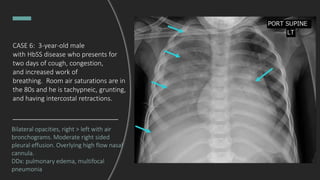

CASE 6: 3-year-old male

with HbSS disease who presents for

two days of cough, congestion,

and increased work of

breathing. Room air saturations are in

the 80s and he is tachypneic, grunting,

and having intercostal retractions.

Interpret this chest x-ray.

Bilateral opacities, right > left with air

bronchograms. Moderate right sided

pleural effusion. Overlying high flow nasal

cannula.

DDx: pulmonary edema, multifocal

pneumonia

Final Dx: Acute chest syndrome